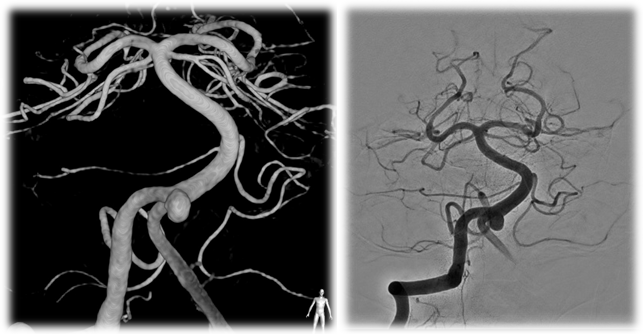

![]() Figure 1-Pretreatment images of the aneurysm |